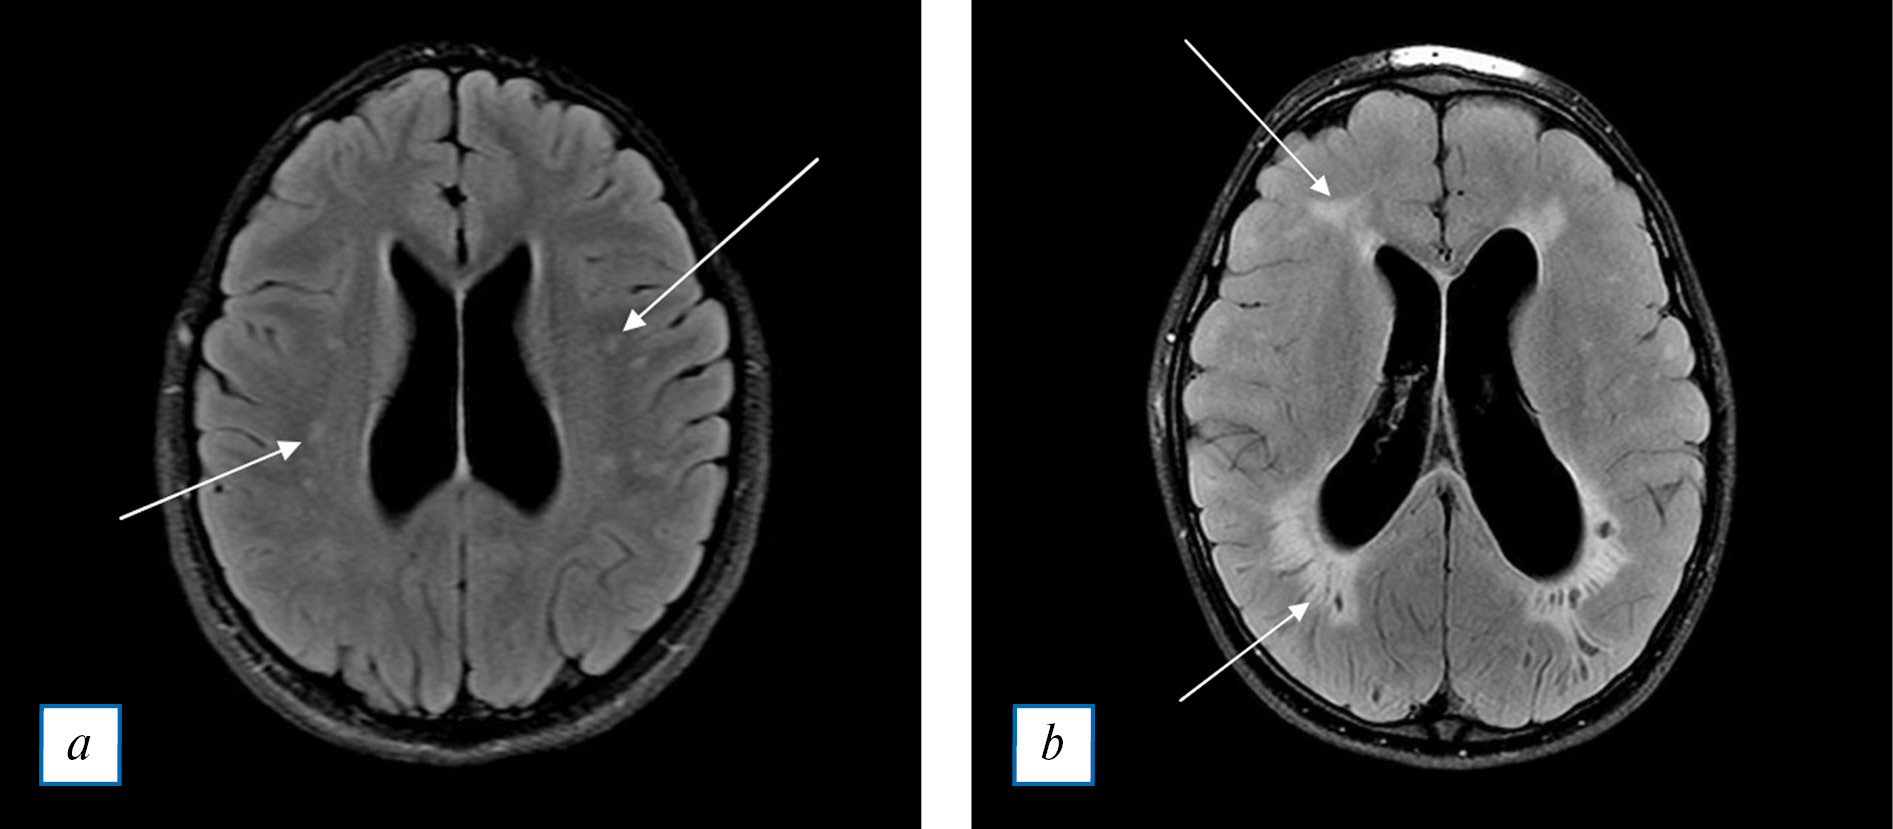

Изменения определяются на Т2-ВИ и FLAIR в белом веществе полушарий в виде симметричных перивентрикулярных гиперинтенсивных очагов (рис. 4, а). Очаги могут сливаться в зоны разной степени выраженности, имитируя лейкодистрофию (рис. 4, б) [14, 17, 26]. Более редко очаги встречаются субкортикально, а также в других долях и отделах мозга.

Рис. 4. МРТ головного мозга, Т2 Flair в аксиальной плоскости: а — стрелками показаны очаги в белом веществе неспецифического характера (у данного пациента они связаны с мукополисахаридозом); b — стрелками показаны перивентрикулярные сливающиеся очаги, симулирующие паттерн поражения при лейкодистрофии. Отмечаются расширенные боковые желудочки и периваскулярные пространства.

Fig. 4. Head MRI, T2 Flair axial plane: a — arrows: non-specific white matter lesions (in this patient, the lesions are related to mucopolysaccharidoseies); b — arrows: periventricular confluent white matter lesions, simulating involvement patterin of leukodystrophy. Dilated ventricles and perivascular spaces are also noted.